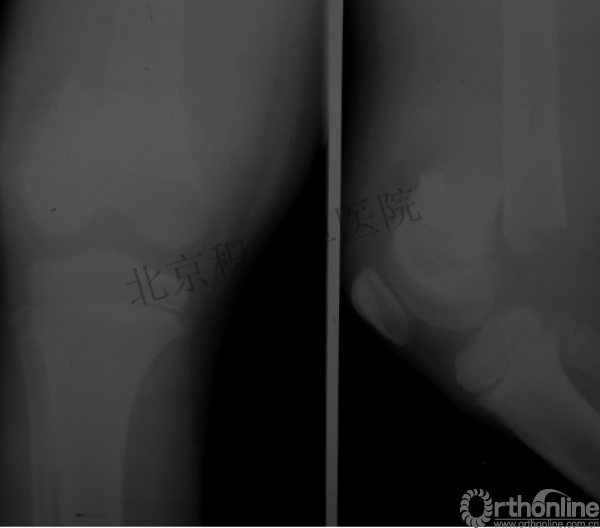

男孩、9岁,滑雪受伤,胫腓骨螺旋形骨折(粉碎性)

这个病例郭教授在积水潭医院骨科高研班时多次讲到,也在互动交流中惊人地看到,了解到现实之令人难以想象!

手法整复,石膏制动!

整复后7天

儿童具备强大的愈合潜力,同样也有极强的塑形能力